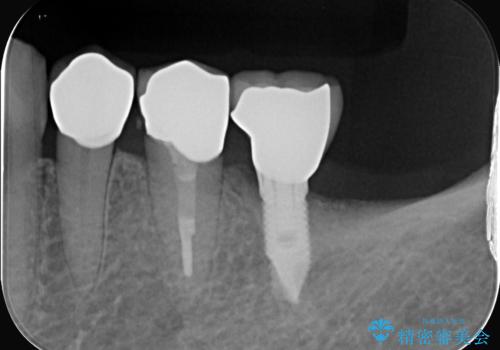

- 主訴:歯茎付近の知覚過敏が強くてどうにかしてほしい

左下4番目の歯の歯頚部に強い知覚過敏症状が出ており、沁み止め材の塗布では症状緩和が望めない状態でしたので、セラミッククラウンで覆う処置としました。

左下4番の歯頚部に知覚過敏症状を認めました。

5級窩洞のコンポジットレジン修復を過去に行ったおり、そのレジンも一部欠けてしまっている状態でした。

咬合力、食いしばりが強く他の歯にも知覚過敏症状が出ているような口腔内で、審美性良く劣化しない丈夫な修復を希望されたため、セラミッククラウンでの治療となりました。